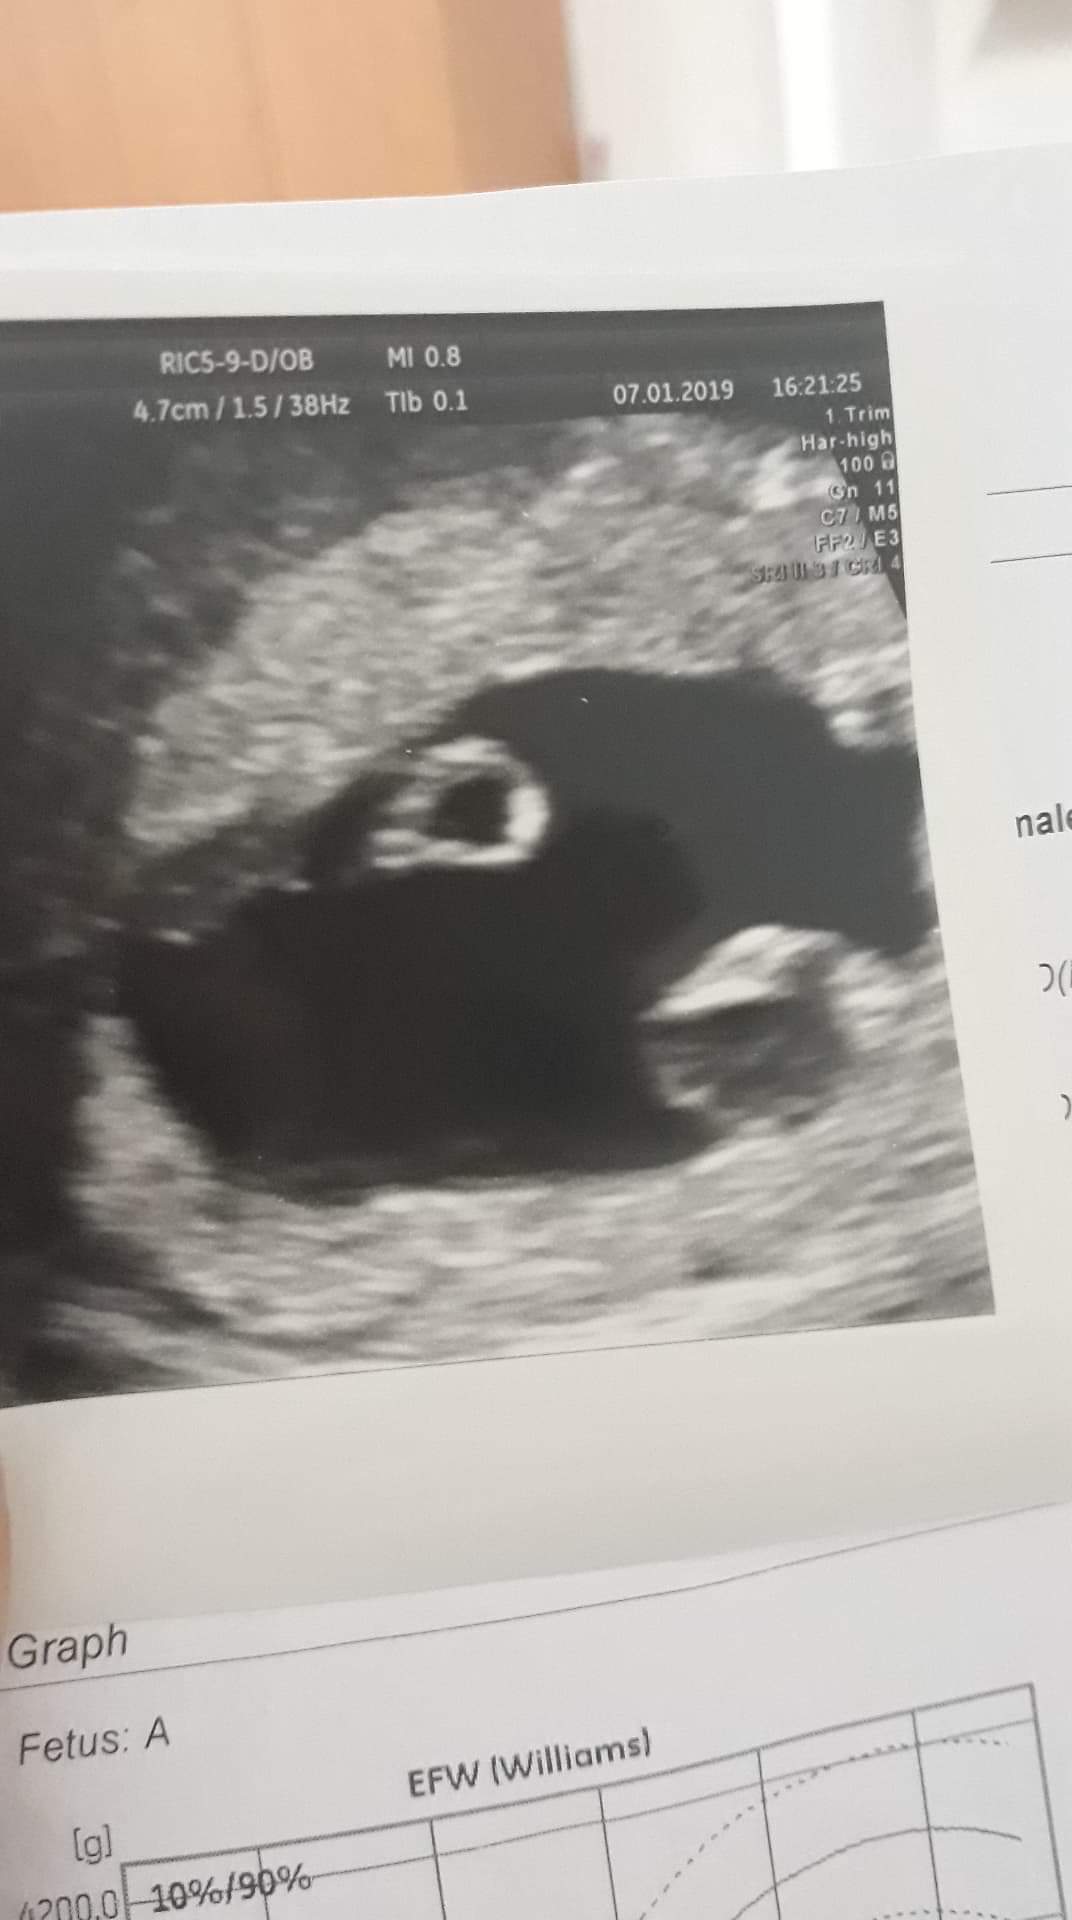

Witam, 2 tygodnie temu podczas usg, lekarz zauważył pecherzyk ciazowy, ale po przeciwnej stronie jakis twór o srednicy 7mm. Kazał pokazac sie za tydzien, na usg widac bylo bicie serca dziecka, ale ten twór nie zniknął, ale też nie urósł, dalej ma 7mm. Jest unaczyniony. Czy ktos spotkał sie z czymś podobnym? Lekarz zaśniad raczej wyklucza, bo hcg nie rosnie na tyle szybko. Prosze o jak najszybszą odpowiedź. Pozdrawiam i załączam 2 zdjecia z usg :)

received_1238004089680019.jpeg